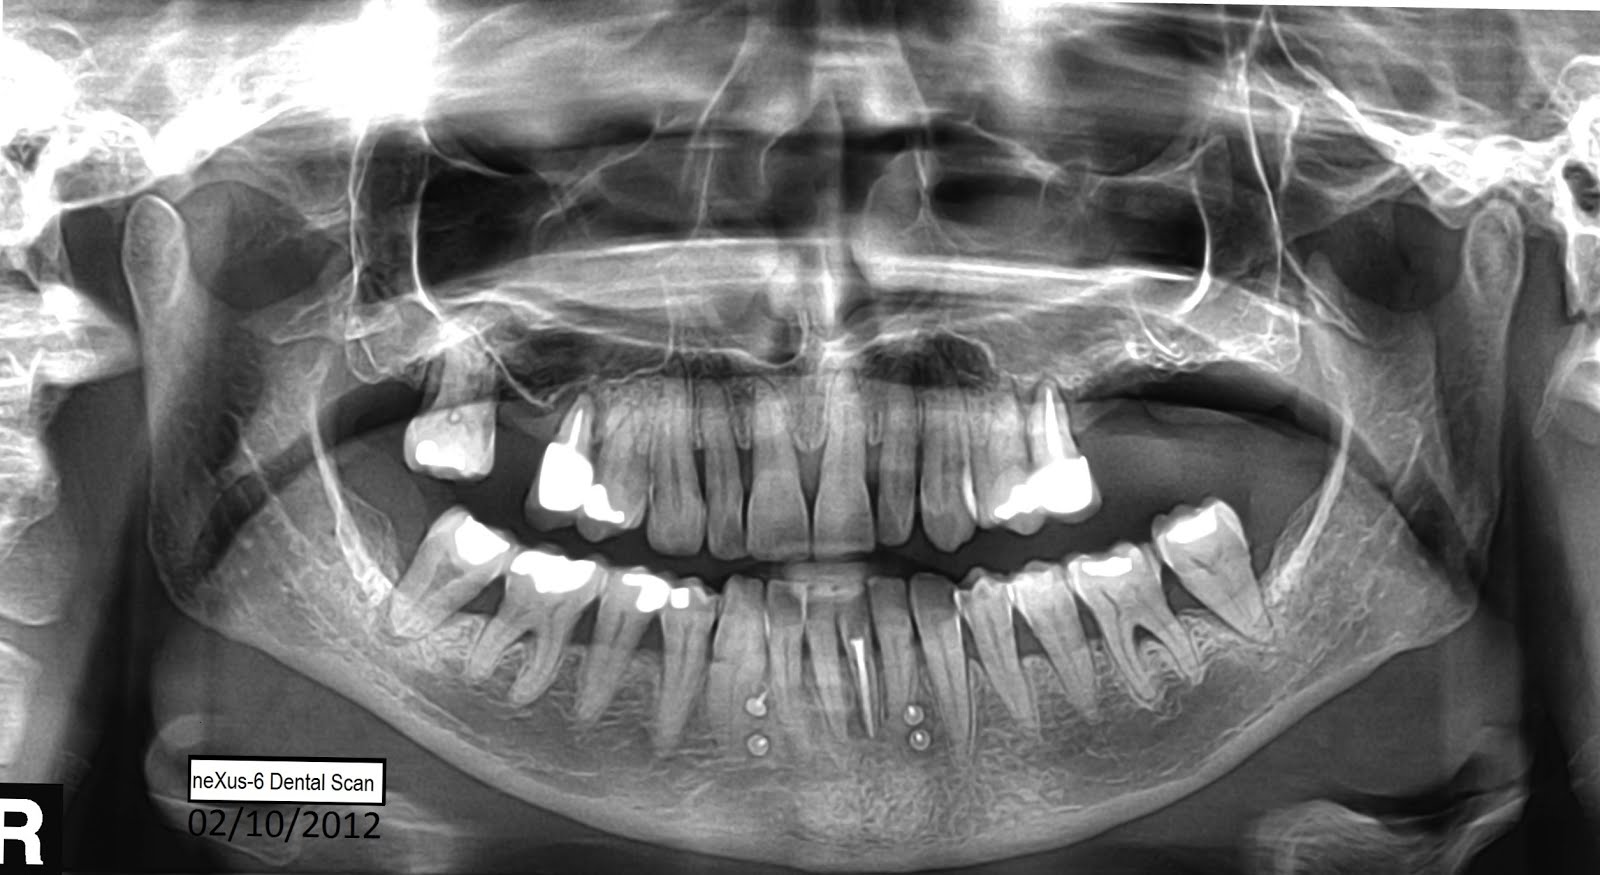

From escanerdental.blogspot.com

neXus6 Dental Scan Centre OSTEOPOROSIS Osteoporosis Dental Problems osteoporosis as a bone disease is initially unlikely to be associated with dental problems. You may be more prone to tooth loss. osteoporosis can affect dental health in the following ways. The risk of sustaining fractures is a concern, and. Nevertheless, the truth is that osteoporosis can very easily affect. jawbone loss due to osteoporosis can result. Osteoporosis Dental Problems.